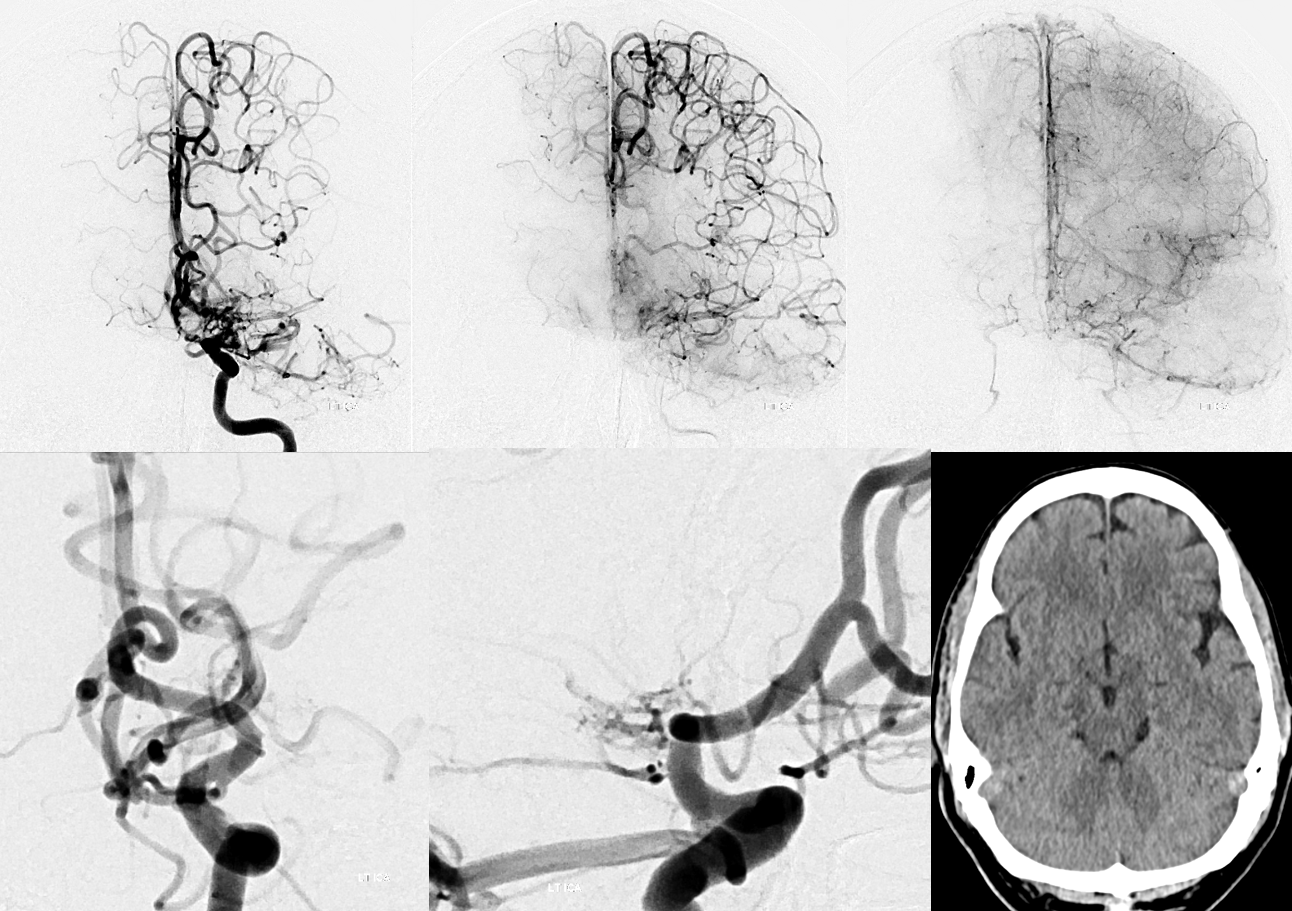

AP and Lateral views (Stereo pair on top) of a temporal lobe avm with deep anterior choroidal supply component.

Anterior Choroidal – Posterior Lateral Choroidal anastomosis — the anterior choroidal beyond the plexal point supplies the plexus of the temporal horn, where it is in balance with the posterolateral choroidal going to the atrium region. This is elegantly shown in the following case of left choroidal plexus AVM, supplied by both vessels with beautiful illustration of draining veins.

Red=anterior choroidal; yellow = posterolateral choroidal; pink=choroidal vein; light blue=inernal cerebral vein; brown=basal vein to sylvian veins; dark blue = atrial vein; white = superior petrosal sinus; green = midbasilar agenesis